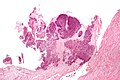

Chondrocalcinosis. H&E stain. | |

| LM | crystals with a rhomboid-shape; polarized light: positively birefringent, blue when aligned |

Microscopic

Features:

- Crystals with a rhomboid-shape.

- Positively birefringent, blue when aligned.

Notes:

- Memory device: ABC+ = aligned blue is calcium & cuboid - positively birefringent.

Micro

The soft tissue section shows readily apparent rhomboid-shaped crystalline deposits (compatible with pseudogout). The crystals polarize and have a light blue hue under polarized light. Synovial hyperplasia is present. No lymphoid aggregates are apparent.

The bony section show thin bony trabeculae and cartilage with degenerative changes (surface fibrillation, thinning).